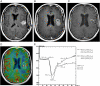

We examine the role of dynamic susceptibility contrast (DSC) magnetic resonance imaging (MRI) perfusion in differentiating pseudoprogression from progression in 20 consecutive patients with treated glioblastoma. MRI perfusion was performed, and relative cerebral blood volume (rCBV), relative peak height (rPH), and percent signal recovery (PSR) were measured. Pseudoprogression demonstrated lower median rCBV (P=.009) and rPH (P<.001), and higher PSR (P=.039) than progression. DSC MRI perfusion successfully identified pseudoprogression in patients who did not require a change in treatment despite radiographic worsening following chemoradiotherapy.